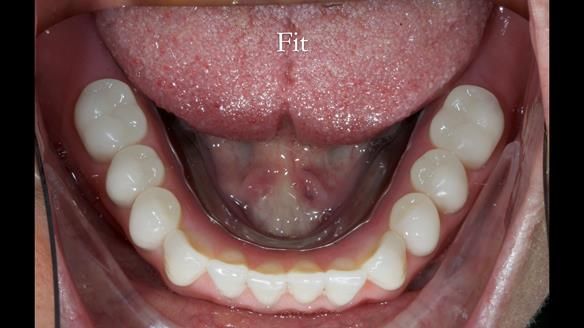

In this edition, I present the complete denture treatment for Kate, a 69-year-old American woman living in Garstang, UK. Kate had been edentulous for many years and required a set of complete dentures that closely mimicked her natural teeth. The new upper and lower dentures provided excellent retention and stability, with significant suction in the upper denture. Below, I detail the step-by-step process of her treatment, as well as my workflow for implant-supported overdentures for patients who may require them.

The treatment was a resounding success, meeting all of Kate’s expectations. While I was confident I could achieve a natural appearance, the challenges of gagging, denture stability, and eating were less predictable and uncertain. I discussed these concerns thoroughly at the outset, and Kate decided to proceed despite the high cost. She expressed that there was no pressure to move forward with the treatment, and she’s been delighted with the life-changing results.